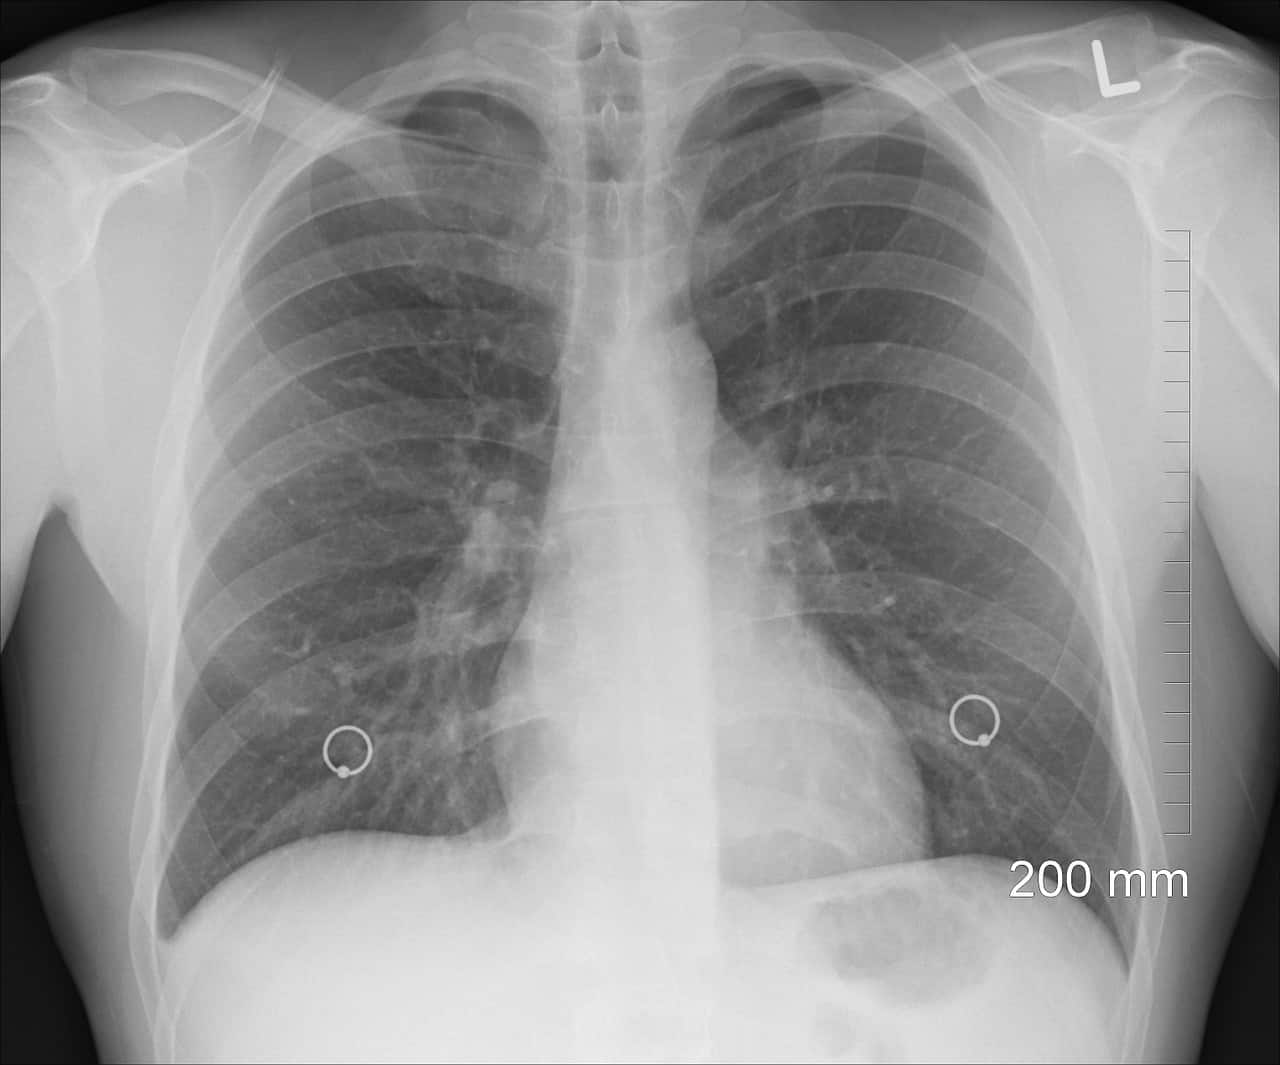

One remarkable sign of bullous emphysema is seen through a chest x-ray. According to experts, the giant bullae often appear to make the lungs disappear. For this reason, many doctors also call bullous emphysema the “vanishing lung syndrome.”